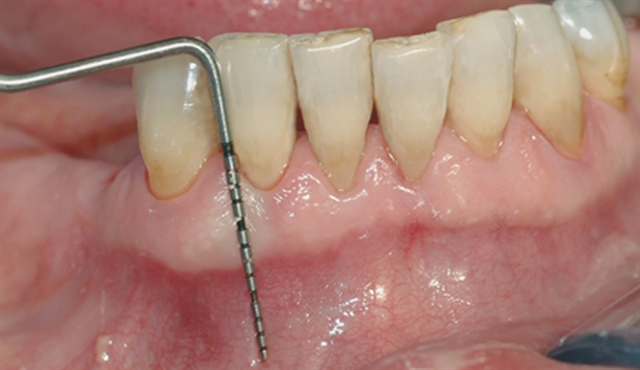

• Biletet viser tilsynelatande normale tannkjøttilhøve ved tenner i underkjeven.

• Ei undersøking med lommeregistrering avdekkjer likevel eit omfattande beintap ved den eine

tanna.

• Instrumentet er her lagt utanpå tannkjøtet for å vise kor omfattande festetapet er.